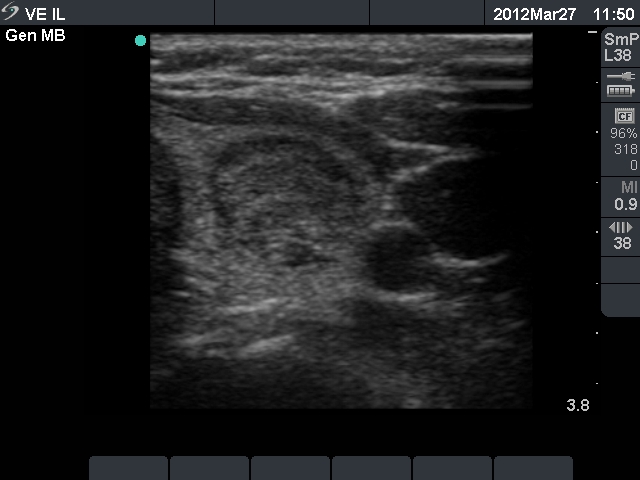

Ultrasonography: the thyroids were echonormal and contained multiple small hypoechogenic lesions. There was a mixed moderately hypoechogenic-echonormal nodule in the left lobe. The nodule exhibited a halo sign and peri- and intranodular blood flow.